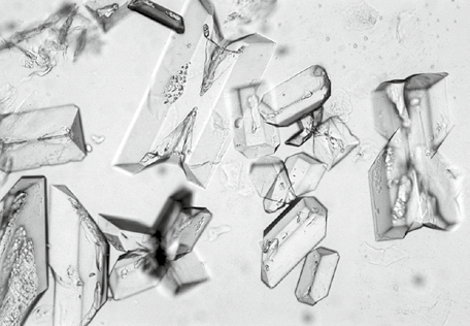

图4 鸟粪石晶体,高倍放大。可看到该晶体的三维结构。